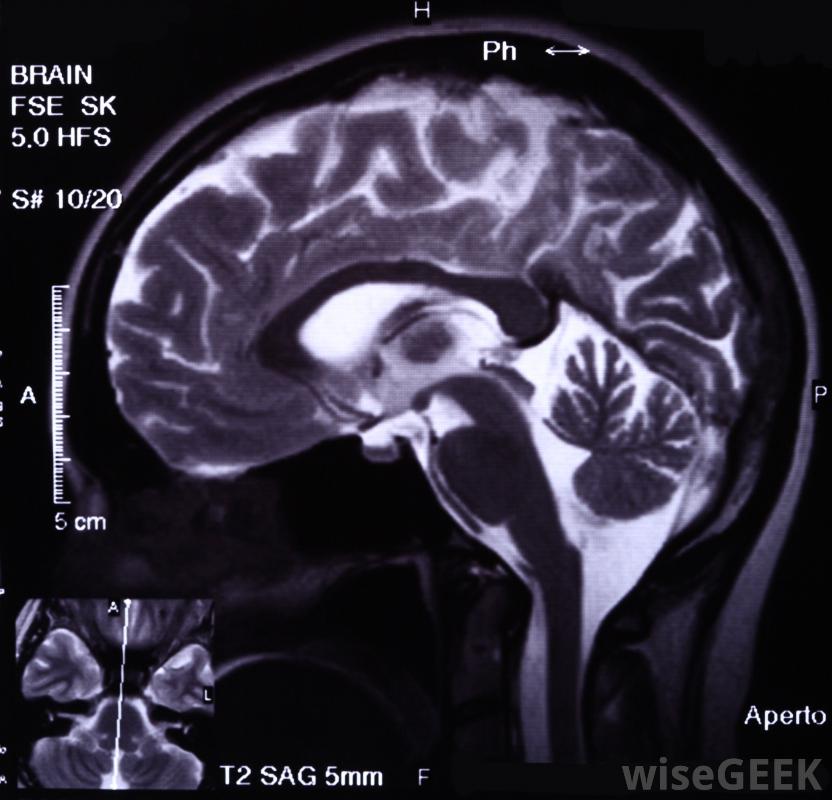

神经心理学是研究人类行为和认知功能变化的学科,通常是在大脑受到某种物理损伤之后。因此,它是心理学和临床神经学的交叉点。在很大程度上,神经心理学是一门应用科学,大多数神经心理学专家都在积极地帮助病人进行临床治疗。除了临床治疗之外,神经心理学家还可以在法庭案件中积极诊断人们的行为变化,深入了解产品设计中的心理反应,研究健康患者对刺激的反应,PET和功能磁共振成像通常被用来检查大脑中可见的问题在临床研究中,神经心理学经常检查患有某种脑损伤的人。通过观察病变的类型、受影响的区域和症状,这项研究有助于进一步了解大脑的不同区域是如何影响行为和认知的,这项工作在过去20年里帮助建立了一个更好的大脑地图,并为神经心理学家提供了更好的工具来完成他们的工作

神经心理学专家可能会对头部受伤的患者进行治疗当面对一个患有某种认知障碍的病人时,神经心理学家所承担的第一个任务是试图发现这种障碍是由实际的生理病理引起的,还是纯粹是一种心理障碍。这是通过使用心理和神经工具来完成的。例如,一个病人他们可能会进行一些不同的标准化测试,考察他们的记忆功能、广泛的智力、视觉保持能力和单词联想能力。他们还可能接受功能性磁共振成像(fMRI)测试或正电子发射地形图(PET)测试,看看大脑是否存在明显的问题神经学是一门医学专业,主要研究大脑和人类神经系统其他部分的状况多年来,神经心理学已经开始越来越有效地利用计算机模拟。这种神经心理学方法被称为连接主义,它使用复杂的人工神经网络在非常基本的水平上模拟人脑。一旦开发出一个合理的模型,它就可以被人为地破坏,虽然没有人工神经网络能接近完美地模拟人脑,但精细的控制水平和所产生的数据使连接主义成为了解更多有关脑损伤后果的有效方法虽然大部分神经心理学都是在临床层面上进行的,但大多数人的兴趣集中在实验神经心理学上。这所学校研究的是健康人,而不是那些遭受某种脑外伤的人,并观察它们对不同输入的反应。这样做是为了更好地了解我们的大脑是如何工作的,以及它们是如何受到我们神经系统反应的影响的,这反过来又可以帮助临床研究人员发现新的治疗方法和治疗方法。由于其受欢迎的性质,实验神经心理学家进行了研究神经心理学涉及到各种各样的测试。